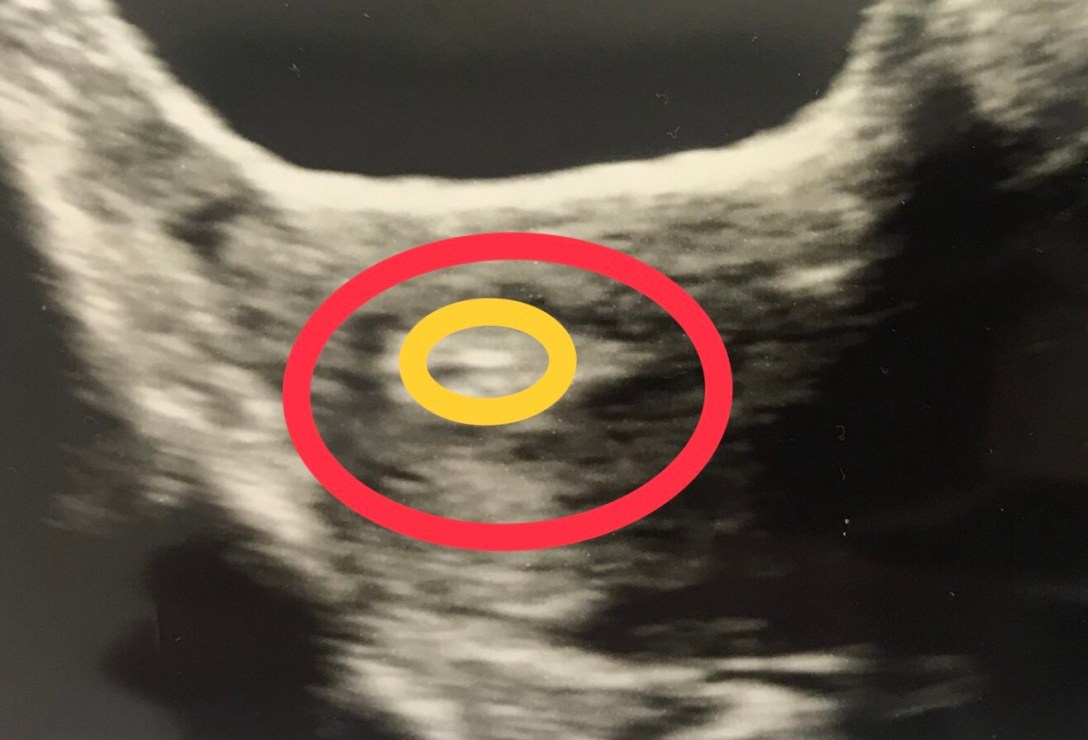

At the embryo transfer the embryologist let us know that the embryo was now 4 cells of fairly equal size, meaning it had divided well, and there was no fragmentation meaning it was good quality.

Our one egg had become a good quality embryo, surely this would mean it would continue to grow well and settle into its new environment. I was feeling super positive. I keep reminding myself I have no physiological issue that should prevent good implantation and healthy baby development.

Parts of the transfer itself were a bit complicated, specifically access issues, and the fertility centre director had to step in and take over from the doctor doing the procedure. However the part where the actual embryo is put into my uterus was straightforward and just like that we had an embryo on board.

As it was 2 days old, rather than the normal 5-day blastocyst, the embryo would need to do a bit more growing before implantation.